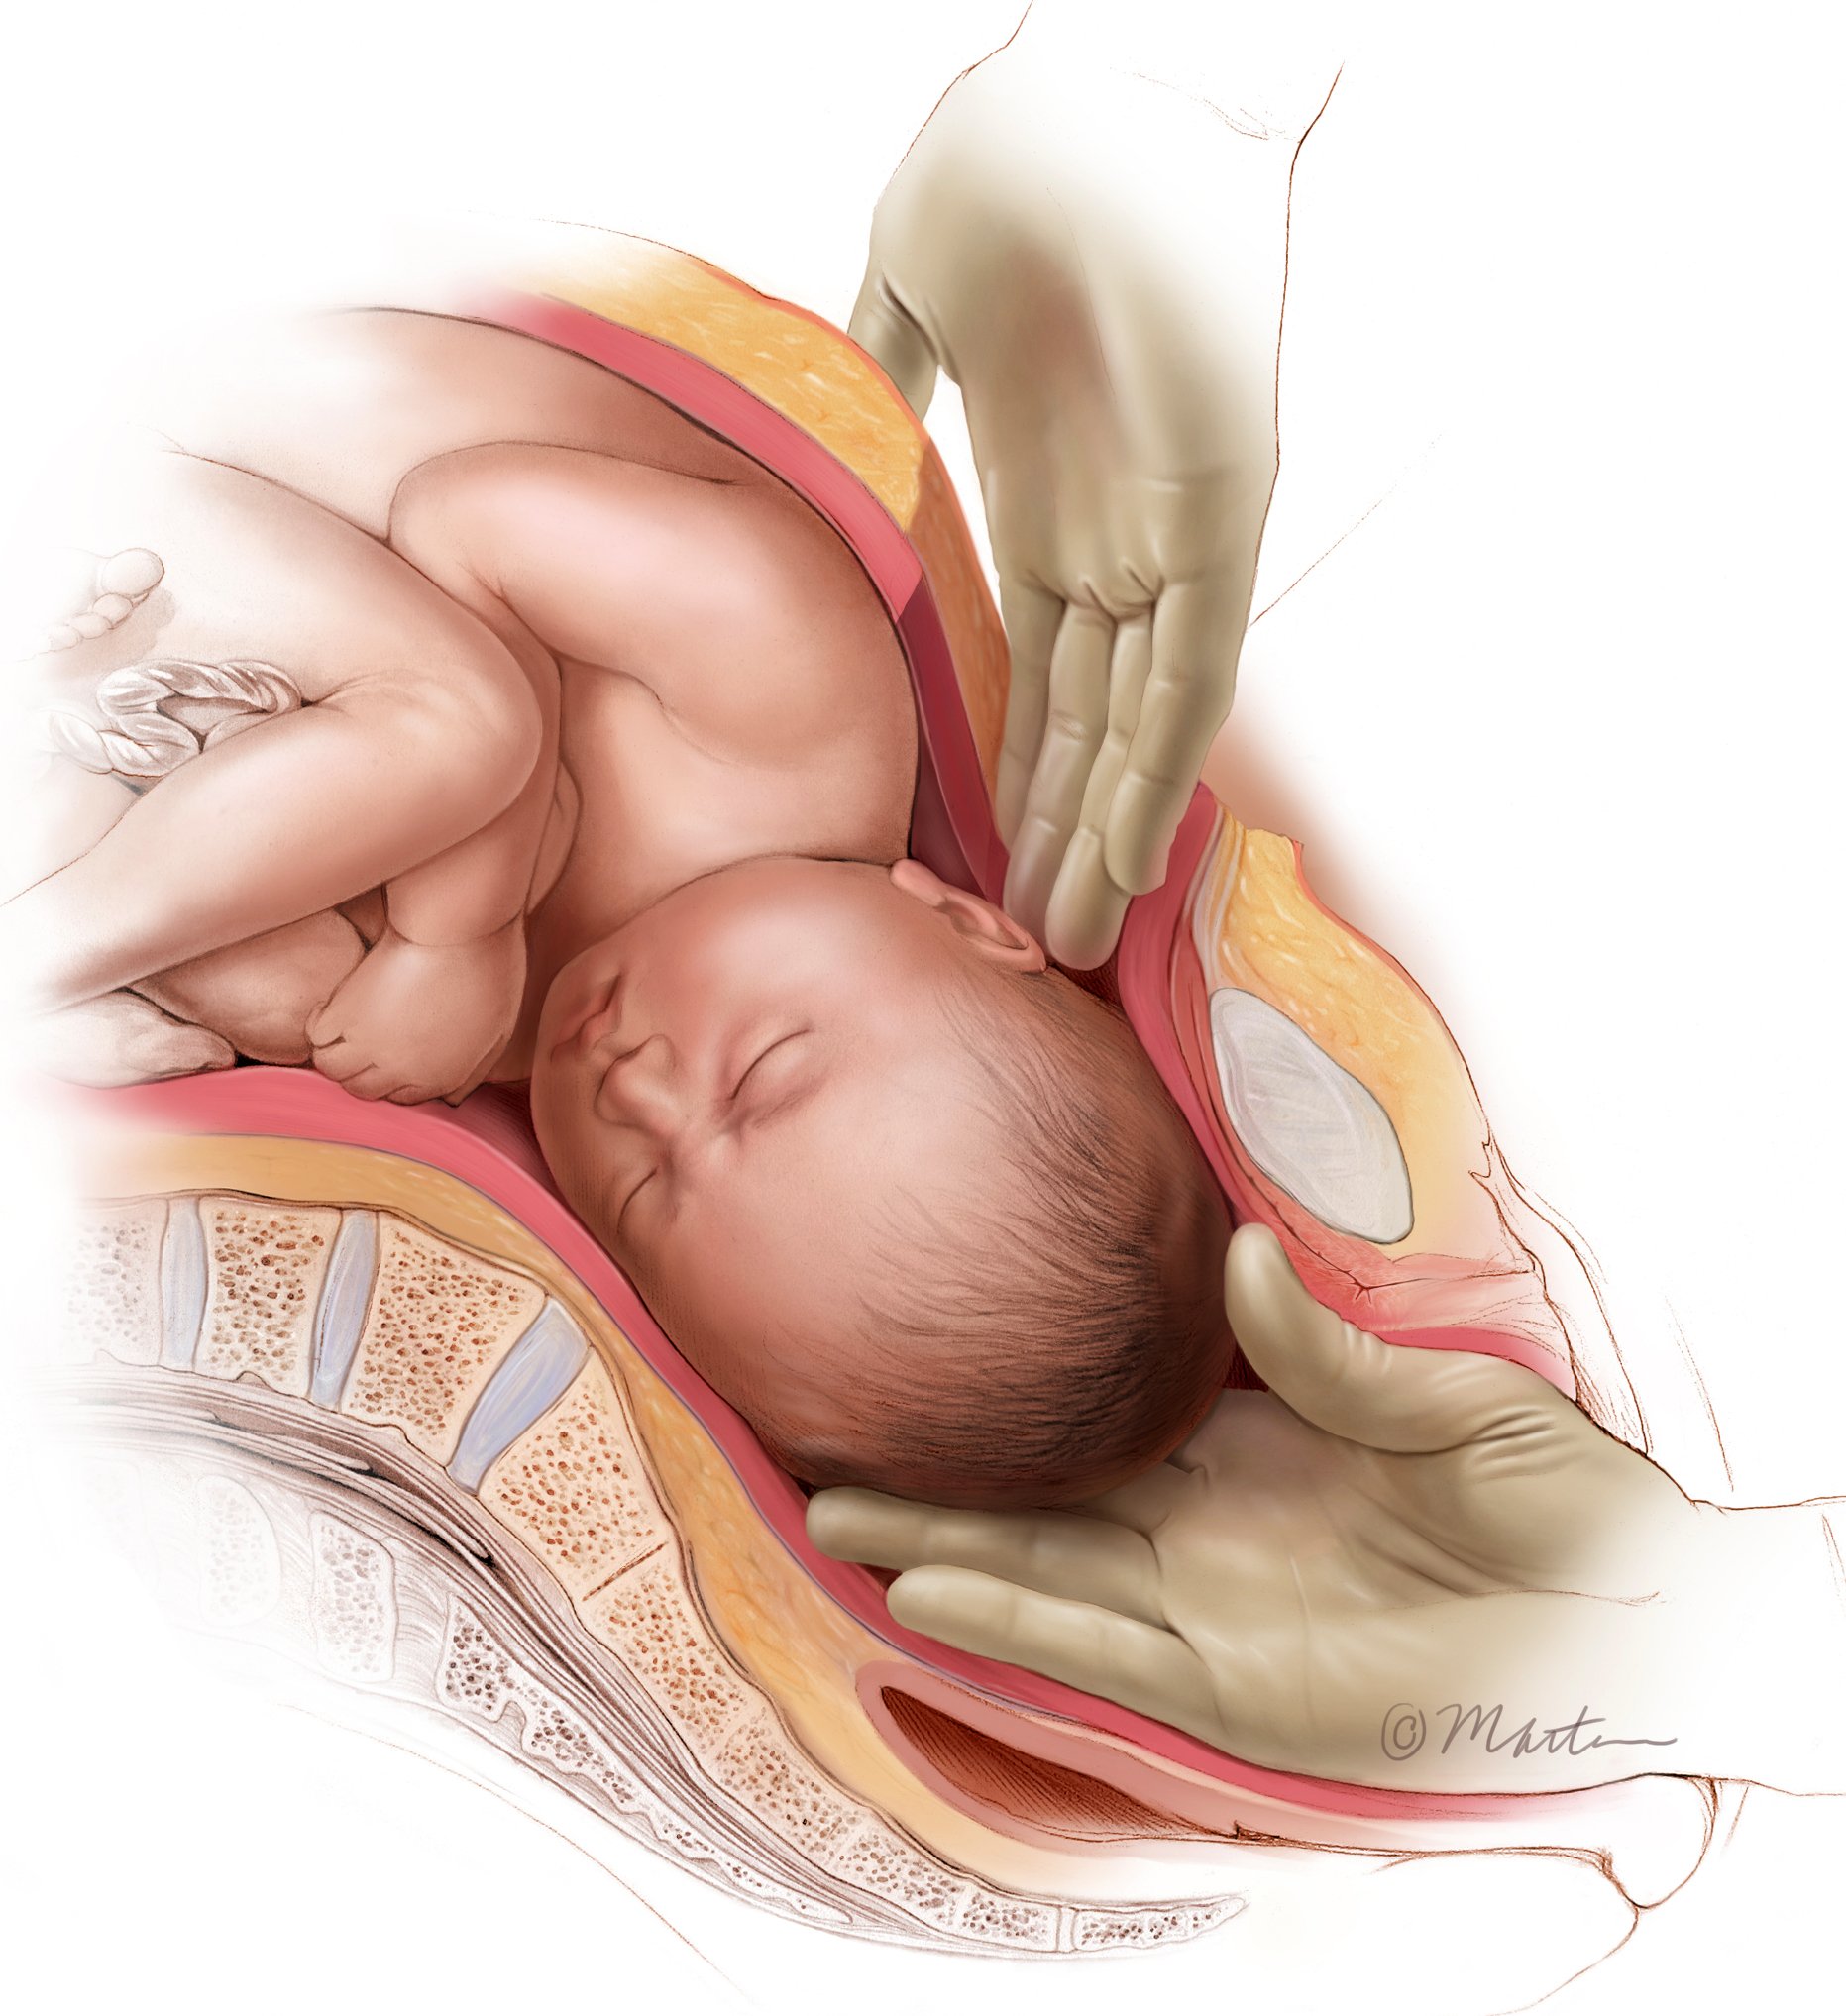

Difficult Cesarean Push Technique